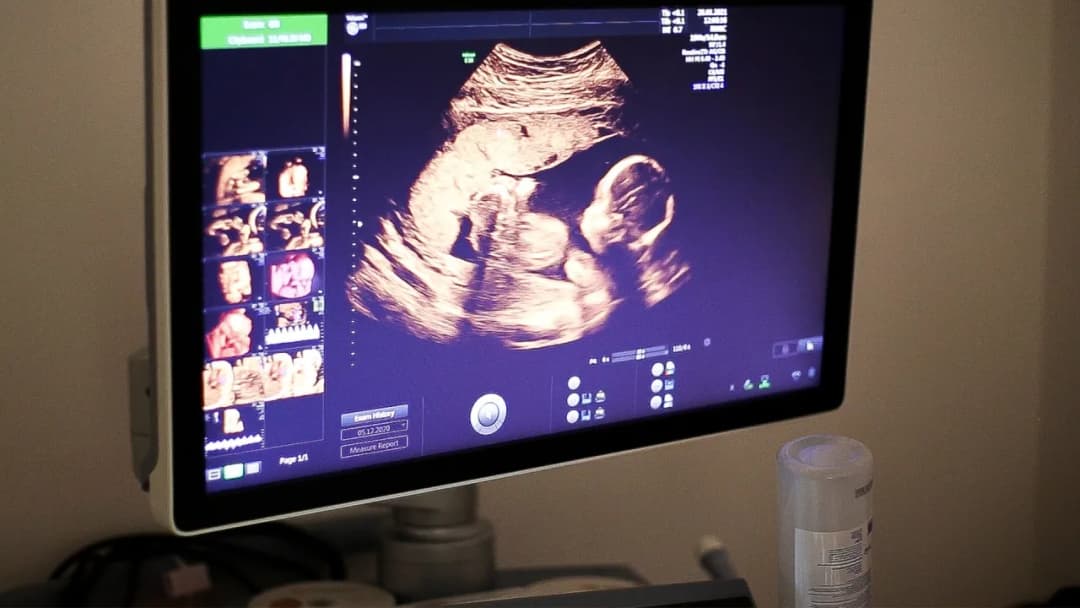

Dowiedz się, jak się robi badania prenatalne. Poznaj metody, ich bezpieczeństwo oraz co warto wiedzieć przed wykonaniem testów.